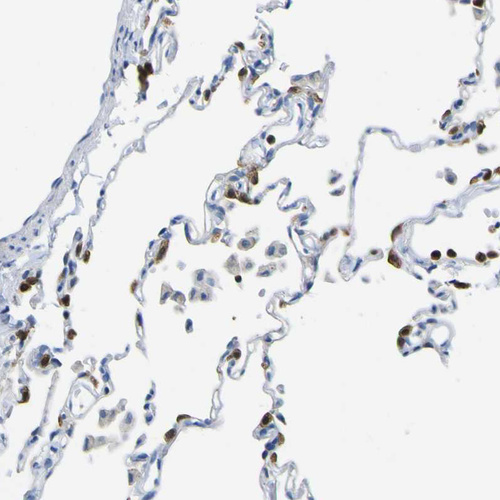

Immunohistochemical staining of human lung shows strong cytoplasmic positivity in pneumocytes.